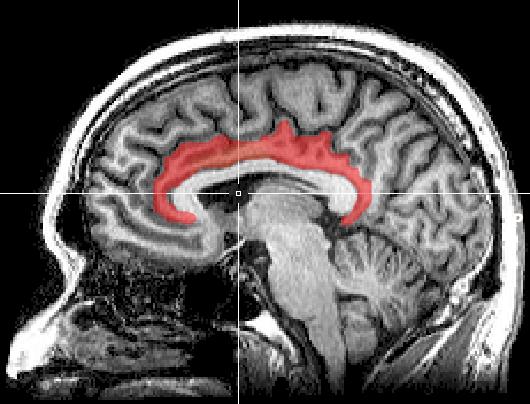

浙江大学的一项功能性核磁共振成像研究为我们揭示了短视频与成瘾之间的关联(如图所示)[4]。该研究对浙江大学的153位抖音用户进行了一次问卷调查。其中,约45.8%的调查参与者存在轻中度的抖音上瘾问题,且有5.9%的人对抖音严重上瘾。统计分析显示,自控能力越差,上瘾程度越高。现代常见的焦虑情感可能会促使人们将小视频视为逃离压力的避风港,而缺乏自控力的人可能更难从这种逃避中抽离出来,进而对短视频产生过度的依赖。

默认模式网络的三个节点与大脑其他区域的功能性连接图示。(a)在观看推荐算法所推荐的视频时,后扣带回皮质(posterior cingulate cortex)与初级视觉、听觉区域,以及一部分顶叶区域的功能性连接增强。(b)相同情况下,内侧前额叶皮层(medial prefrontal cortex)与前扣带回皮质(dorsal anterior cingulate cortex)等其他区域的功能性连接减弱。(c)颞极在颞上回内的功能性连接增强,与楔前叶、腹内侧前额叶皮质(ventromedial prefrontal cortex,vmPFC)等诸多区域的功能性连接减弱。—

参考文献[4]